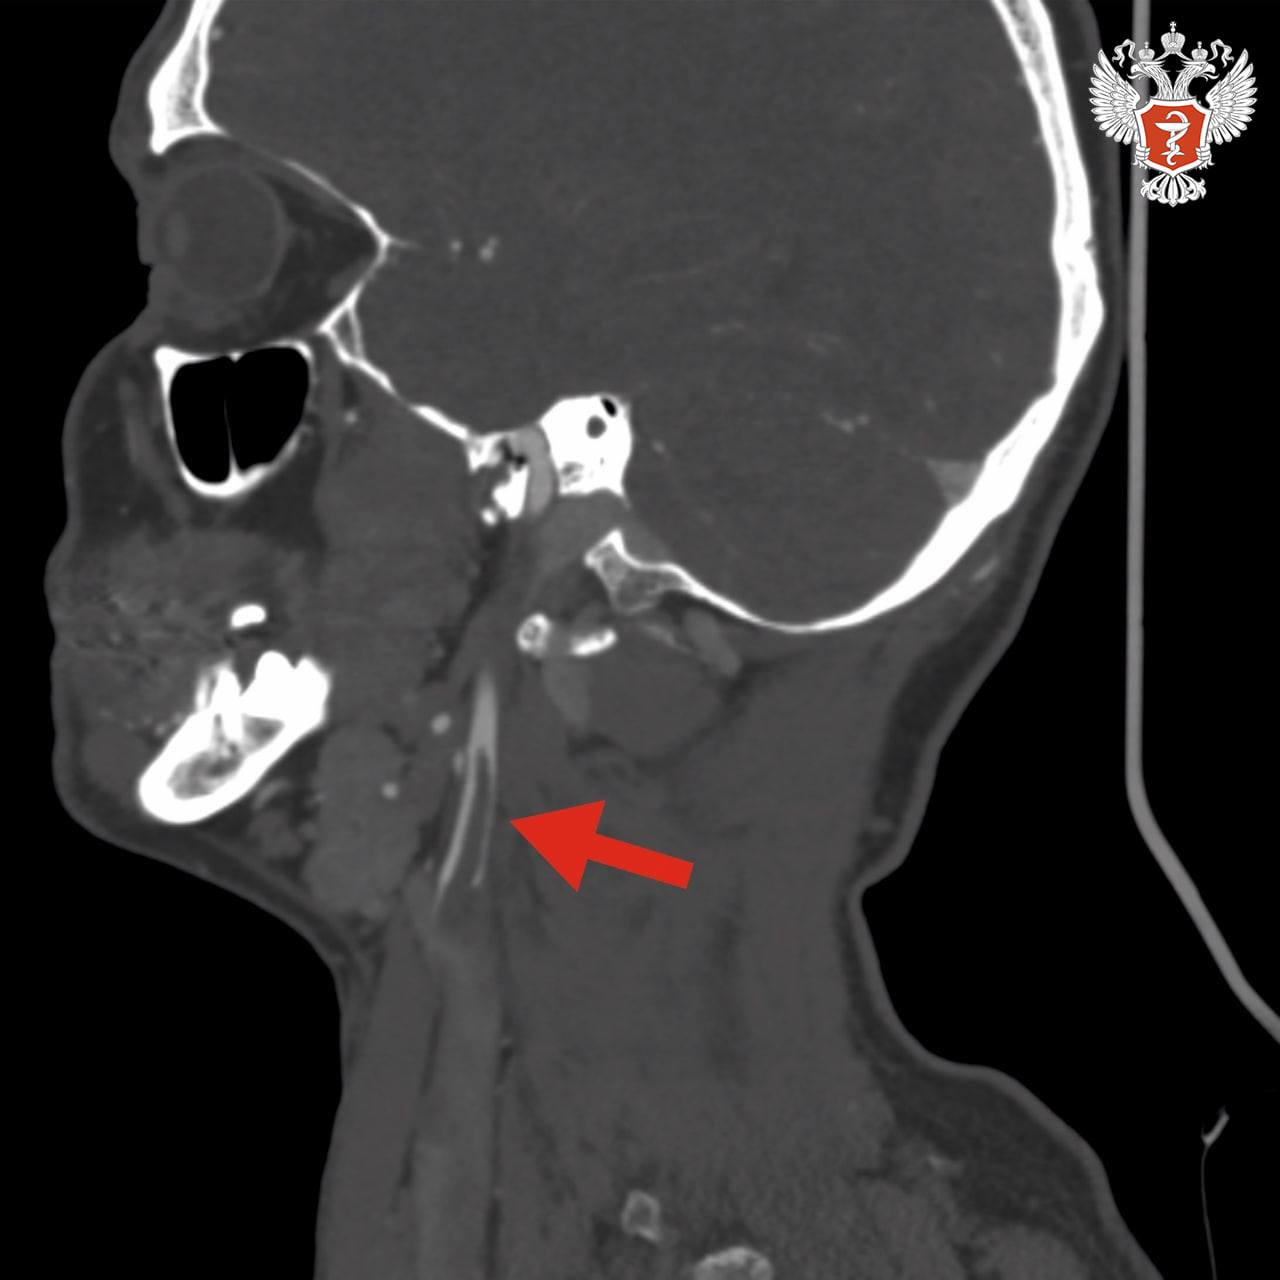

В ходе исследований врачи выявили тромб длиной около 4 см в просвете правой внутренней сонной артерии. Он нарушал кровоснабжение головного мозга. В любой момент тромб мог оторваться и закрыть магистральные артерии правого полушария, что привело бы к обширному ишемическому инсульту.

Хирурги экстренно провели операцию и удалили тромб, изъязвленную атеросклеротическую бляшку во внутренней и общей сонных артериях и восстановили анатомию сосудов.